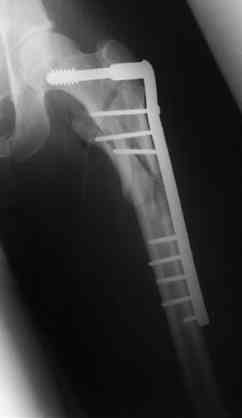

Бедро фиксировал длинной DCS.

По типу бриджинг плэйтин, крюком удалось низвести малый вертел и фиксировать винтом для восстановления медиальной стенки.

В приложении отправляю послеопер. снимки бедра и лодыжки обсуждаемого вчера больного.

В приложении послеоперационные картинки.